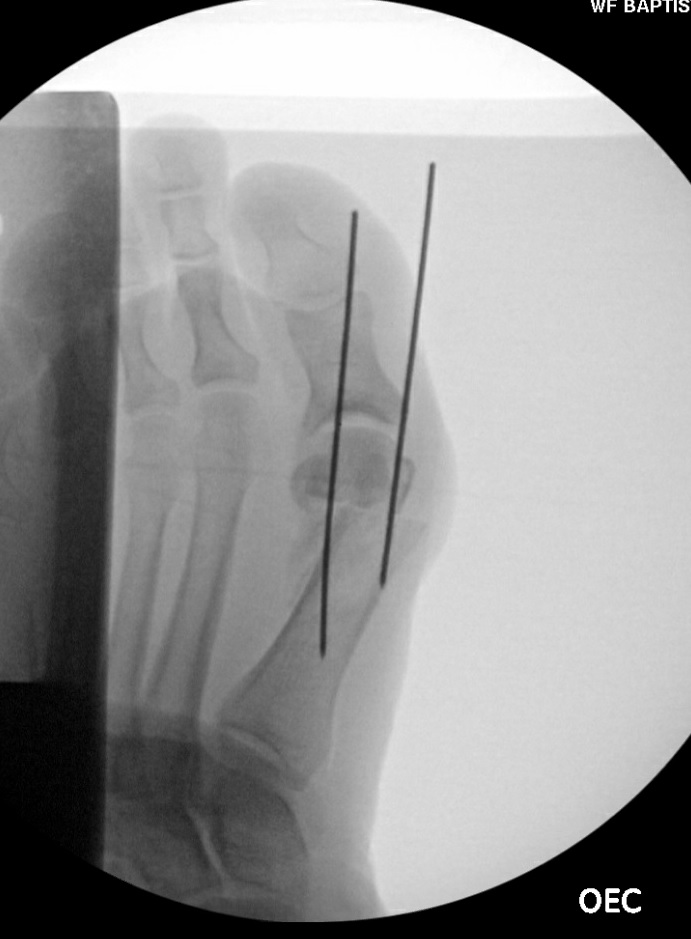

To create the temporary fixation, the surgeon introduces a 0.045-inch K-wire through the dorsal medial cartilage of the metatarsal head and advances it through the proximal dorsomedial metatarsal neck crossing the osteotomy site (see third photo). Next, one introduces a second K-wire parallel to the previous wire from the dorsal lateral cartilage of the metatarsal head and advancing through the proximal dorsal

lateral metatarsal neck crossing the osteotomy site (see fourth photo from top). After confirming satisfactory osteotomy position under fluoroscopy, a guidewire then bisects the "goalpost" created by the temporary fixation. This guidewire traverses from the metatarsal neck dorsal proximal to plantar distal through the osteotomy site and the crista of the metatarsal head.